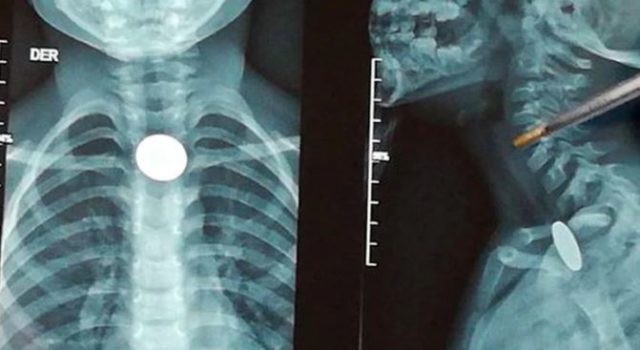

Un nene lleva 7 días atragantado con una moneda y no autorizan su extracción

Un niño lleva una semana atragantado con una moneda en Santander, Colombia. El menor sigue esperando a que el objeto salga por si sola.

Según denunció Amanda Mora, madre del menor, el servicio de salud EPS Salud Vida no autorizó los respectivos procedimientos porque, según ellos, el niño no está sufriendo de una enfermedad grave.

“La EPS me dice que no se puede autorizar el tratamiento en Bucaramanga porque no es algo grave que le afecte su salud, me dijeron que tomando agua el niño podría expulsarla”, dijo la madre del pequeño.

Amanda Mora, quien es oriunda del Sur de Bolívar y que se trasladó a Bucaramanga desesperada por ayudar a su hijo, está solicitando préstamos con entidades bancarias con tal de realizarle el tratamiento endoscópico que le puede extraer la moneda al menor.